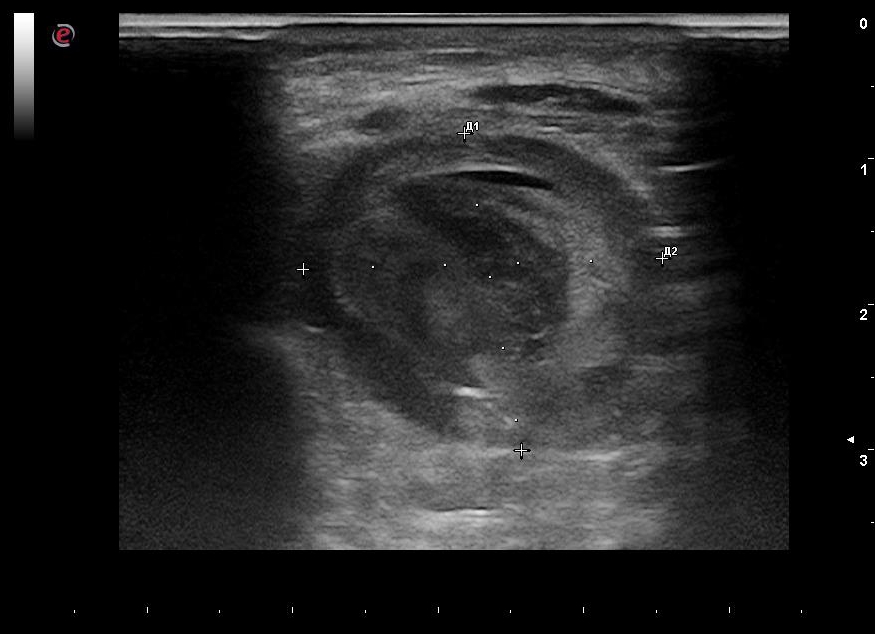

Repeat duplex scanning of the upper limb arteries: the aneurysm cavity spread to the upper third of the upper arm (Figures 3, 4), with the main type blood flow through the RA. Under ultrasound guidance, compression was applied in the area of the pseudo-aneurysm neck.

Fig. 3. Repeat Duplex scan (the second day), color Doppler mode, longitudinal section. The blood flow in the lumen of the radial artery pseudoaneurysm is shown.

Fig. 4. Repeat Duplex scan (the second day), spectral Doppler mode, longitudinal section. The blood flow in the neck of the radial artery pseudoaneurysm is shown.